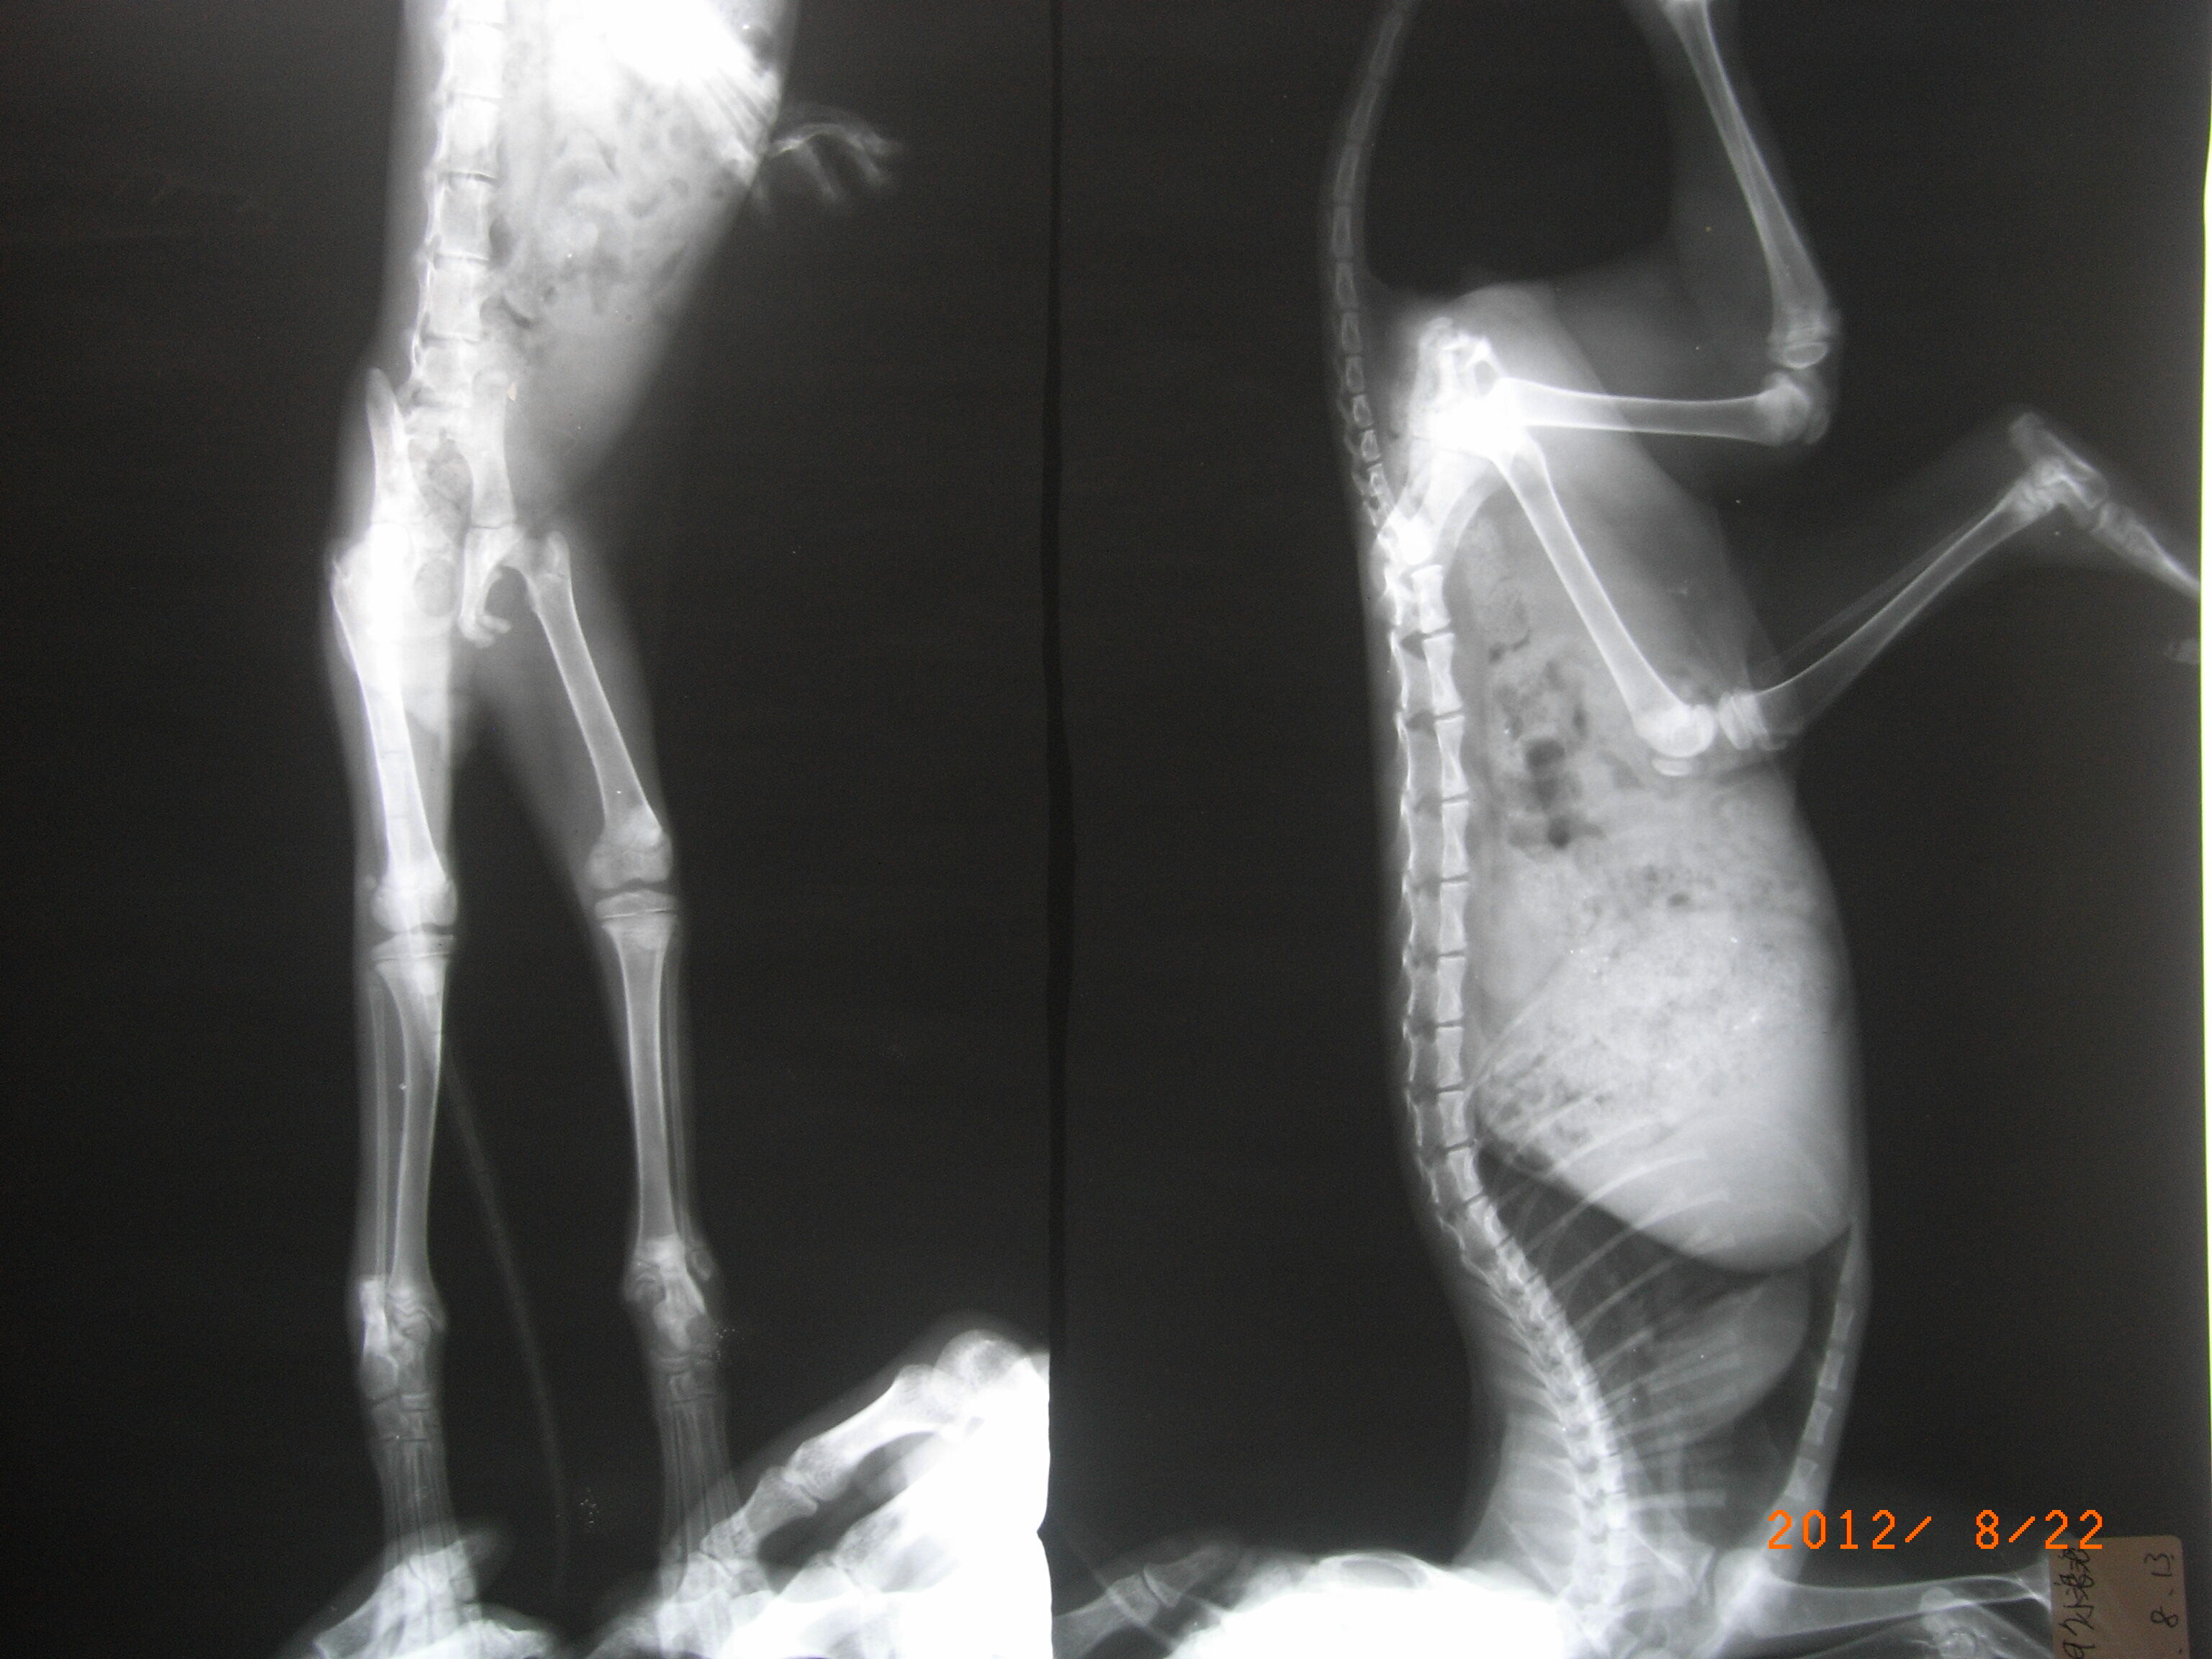

主題: 先天性腳踝有問題的小貓 申請者姓名: 徐慕雯 花色: 申請日期: 2012-08-23 23:28:04 申請者部落格: 申請者臉書網址: 所在縣市/合作醫院: 桃園縣/普羅動物醫院 治療費用: 1115元 需求人數: 4人 已結案 (2012-12-02 16:37:39) 報名人員: Miko Lee(已付款)、Miko Lee(已付款)、Alina Wang(已付款)、謝欣蓓(已付款)、 候補人員: 小舟、 動物病情說明: 這隻小貓是由Mili Huang通報,發現貓咪行走都以半拖行的方式,疑似攤瘓。

送醫檢查並觀察數日後,小貓應是先天性的腳踝腫大,而非外力造成,這個孩子可能要一輩子拖行走路了,但他非常勇敢,也很樂觀哦 ~